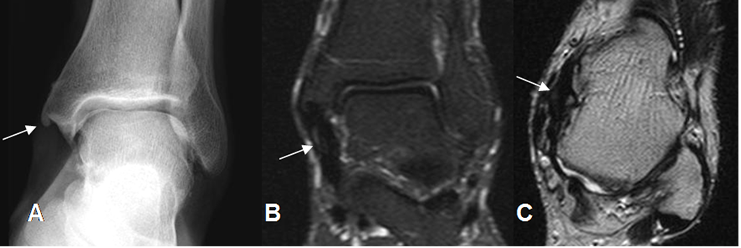

A: RM coronal en T1. Pérdida de la señal normal de los ligamentos peroneoastragalino posterior (Flecha delgada) y peroneocalcaneo (Flecha gruesa).

B: RM axial en T2 y C: RM axial en T1. Los componentes del ligamento colateral lateral están engrosados y con alteración de su señal, por lesión crónica.

Fig 66. Lesión ligamentaria crónica.

A: Rx AP. Calcificación en el borde inferior del maléolo interno y prominencia de los tejidos blandos.

B: RM coronal en STIR y C: RM axial en T2. Engrosamiento del ligamento tibiocalcáneo (Flechas), por lesión crónica, sin signos de ruptura completa.